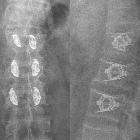

SpineJack-Implantat

in 3 Höhen der LWS